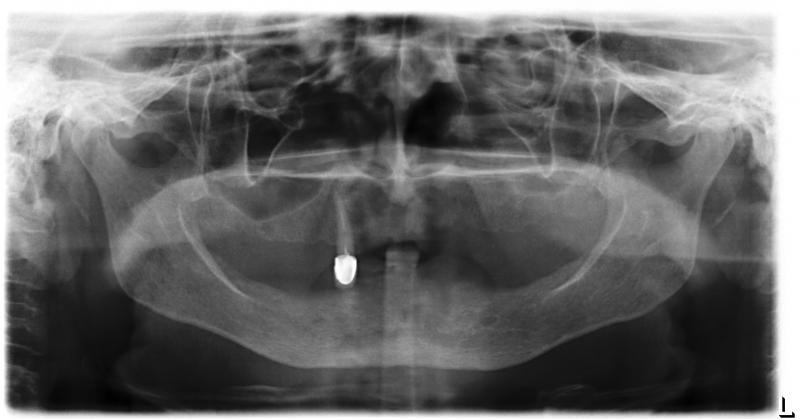

| Фото →Установка 10 имплантантов на беззубую челюсть с помощью компьютерной программы: Первый визит пациентки |